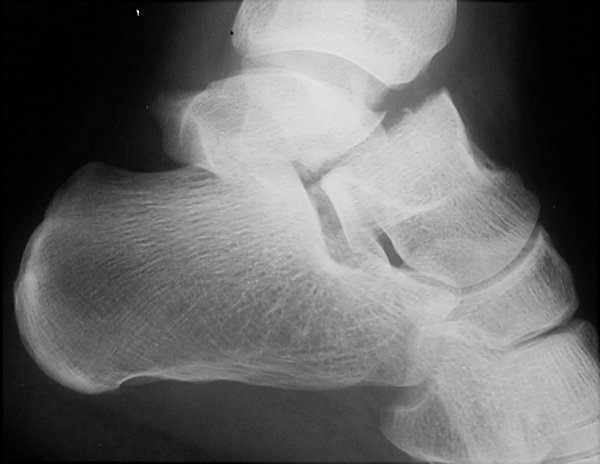

Return to Aviator's Astragalus